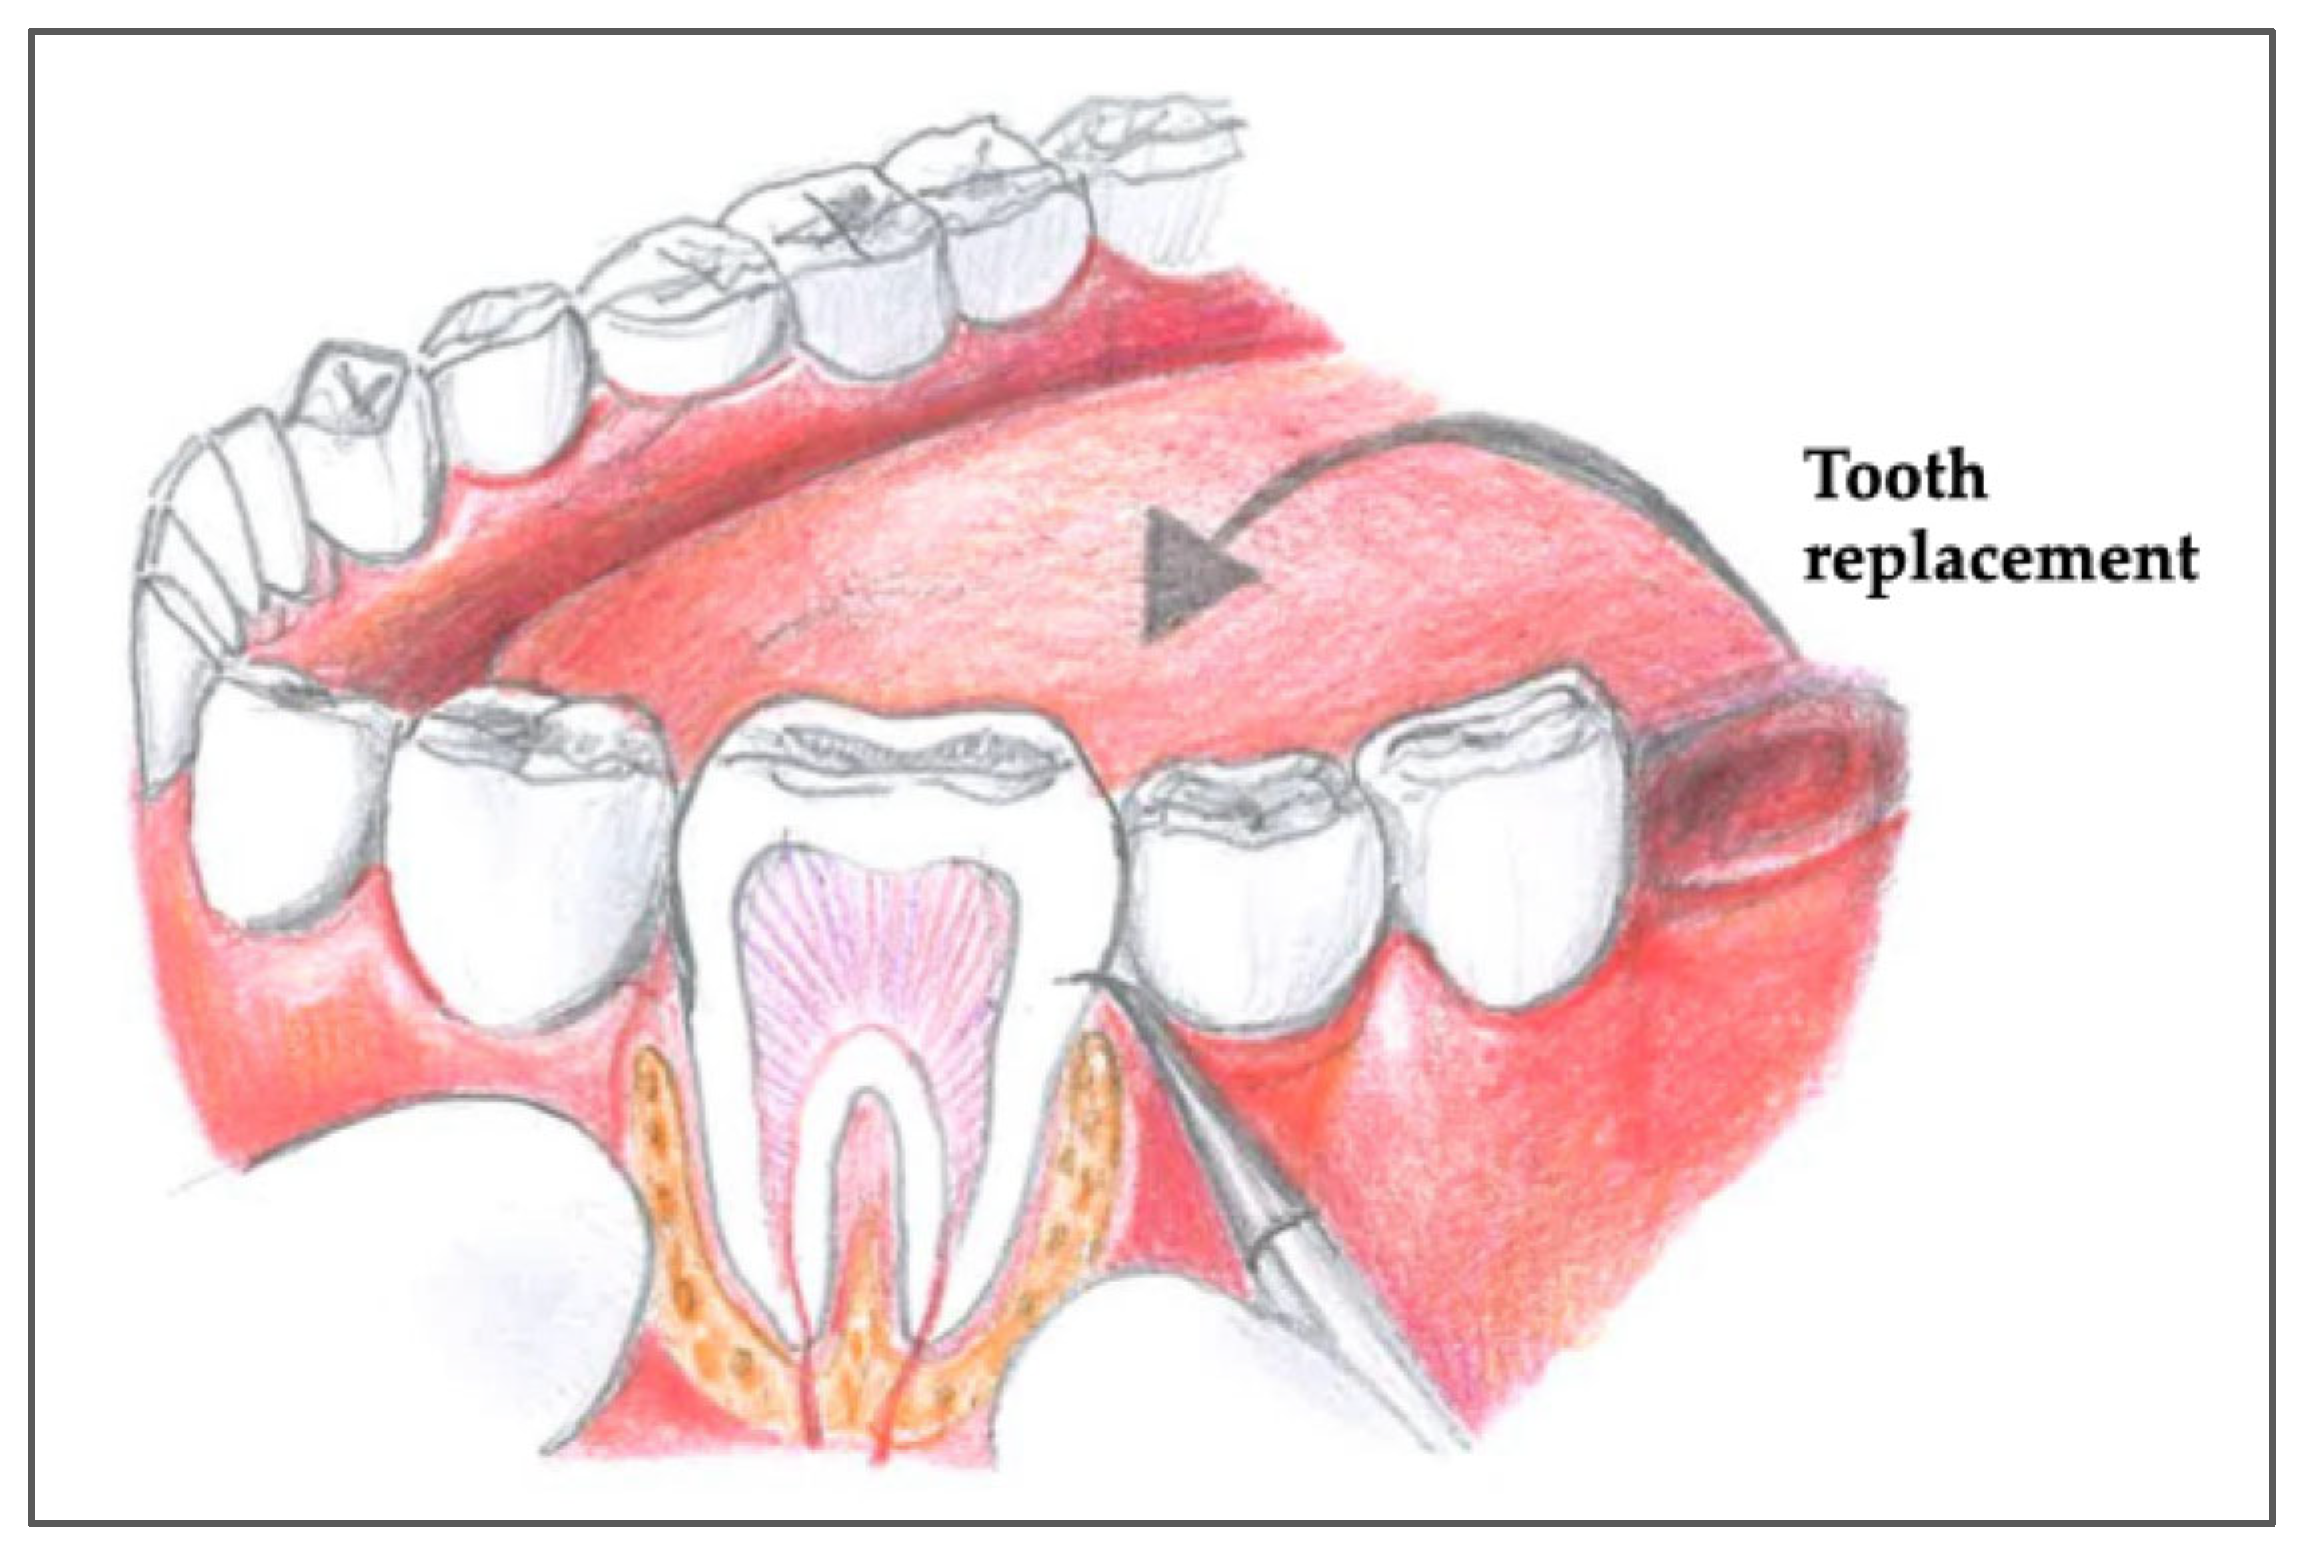

5. A Step-by-Step Surgical Protocol for Tooth Autotransplantation

5.2. Preparation of the Recipient Site

5.3. Atraumatic Explantation of the Donor Tooth

5.4. Insertion and Stabilization of the Donor Tooth